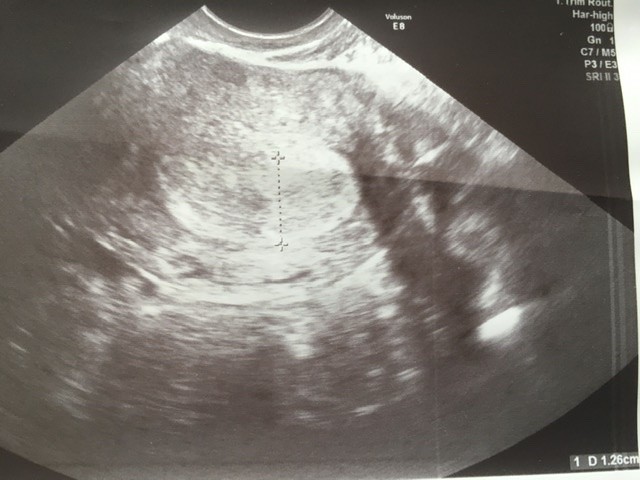

To masz taki sam termin jak ja ja też 8stycznia okres, też byłam na wizycie tylko u mnie USG wygląda zupełnie inaczej, jest taka mała czarna plamka taki groszek. Pusty. U ciebie jest wyraźnie jaśniejszy i większy.Cześć wszystkim, pierwszy raz na forum i nie wiem czy w dobrym miejscu kliknęłam. Może pomożecie? 8 stycznia ostatni okres , owulacja raczej 25 stycznia, Beata 7 lutego 133 i po dwóch dniach 680, (Przy pustym tez może wzrastać) ginekolog stwierdziła ze słabe te jajo i chyba puste, idę we wtorek ponownie. Dołączam fotę co myślicie?Zobacz załącznik 1080823

Wydaję mi się że Tobie beta pięknie urosła i jednak ten dzidziuś tam sobie rośnie...To masz taki sam termin jak ja ja też 8stycznia okres, też byłam na wizycie tylko u mnie USG wygląda zupełnie inaczej, jest taka mała czarna plamka taki groszek. Pusty. U ciebie jest wyraźnie jaśniejszy i większy.